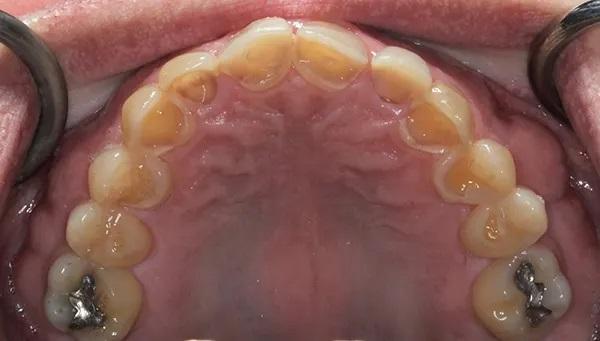

Биомеханика: Сильная эрозия с обнажением дентина была отмечена на язычных поверхностях зубов с 1.4 по 2.4 (Фото 4), а также на лицевой и резцовой поверхностях зубов с 3.6 и 3.3 по 4.6 (Фото 5). В зубе 3.4 ранее проводилось лечение корневых каналов, а на зубах 3.6 и 3.5 были установлены большие реставрации, превышающие треть ширины их перешейка. На зубах с 1.3 по 2.3 имелись сколы. Хотя кариес в зубном ряду пациента не отмечался, потеря структуры зубов привела к серьезным структурным нарушениям во всех зубах, за исключением моляров верхней челюсти. На зубах 1.6 и 2.6 были выполнены окклюзионные реставрации из амальгамы, которые были приемлемы при незначительной эрозии на кончиках бугорков. Зубы 1.5 и 2.5 имели незначительную эрозию на окклюзионной поверхности.

Фото 4: Верхняя челюсть: вид с окллюзионной стороны до лечения Обратите внимание на сильную потерю эмали.